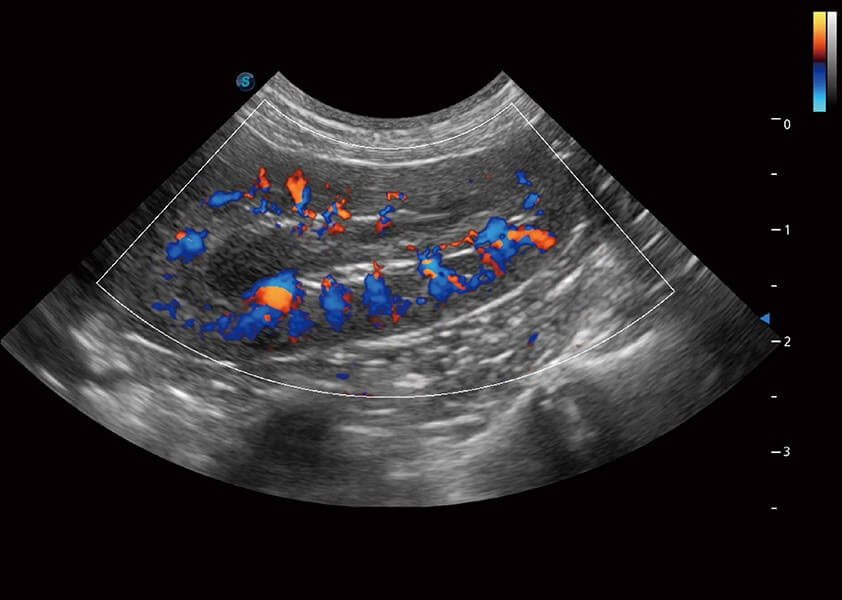

4T血流成像 微察秋毫

融合不同血流成像技術(shù)的優(yōu)勢(shì),即可以提升血流成束性,同時(shí)可提高血流的視覺(jué)敏感性。

PDI 能量多普勒血流

提供高靈敏度和空間分辦率的血流圖像,獲得更加真實(shí)和豐富的診斷信息。

SR Flow 高分辨率血流成像

能夠清晰顯示細(xì)小、低速血流圖像,獲取傳統(tǒng)彩色多普勒技術(shù)難以得到的細(xì)節(jié)和信息。

Micro F 顯微血流成像

通過(guò)創(chuàng)新的Matrix E自適應(yīng)濾波器和超長(zhǎng)時(shí)間域算法,極大提升超低速微細(xì)血流的檢出能力,同時(shí)更精準(zhǔn)地濾除軟組織和噪聲信號(hào),為獸用醫(yī)生提供以往無(wú)法通過(guò)常規(guī)血流獲得的疾病診斷信息。

Bright Flow 立體血流成像

在傳統(tǒng)二維血流成像的基礎(chǔ)上,呈現(xiàn)血流的立體感,具有動(dòng)感的生命力之美。精確區(qū)分不同血管的空間關(guān)系,提高了血流的視覺(jué)敏感性。

(犬)腎臟血流